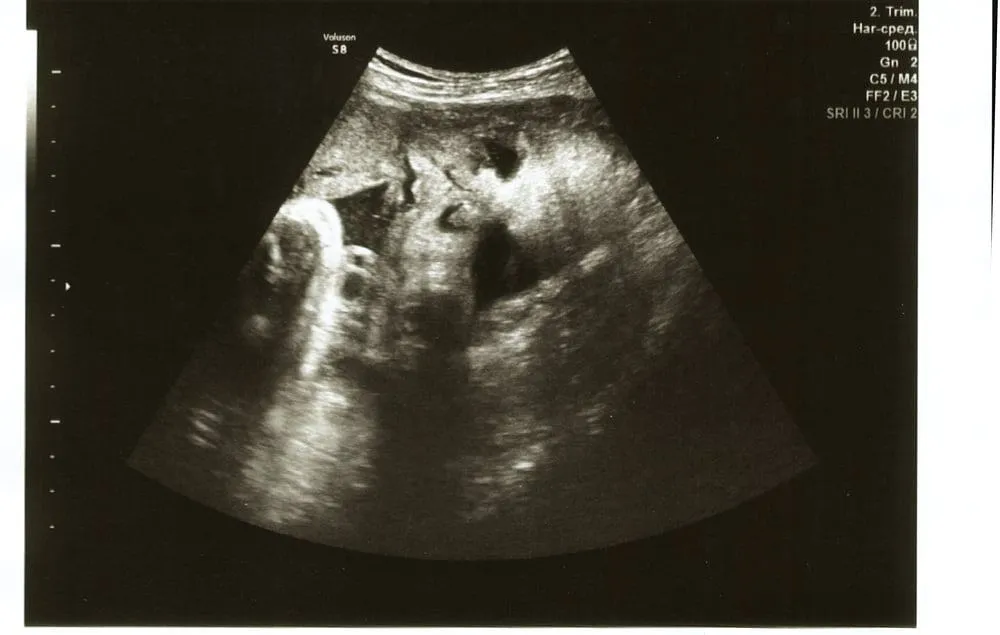

Thông qua siêu âm, mẹ cũng có thể quan sát được hình ảnh thai nhi 33 tuần trong bụng mẹ.